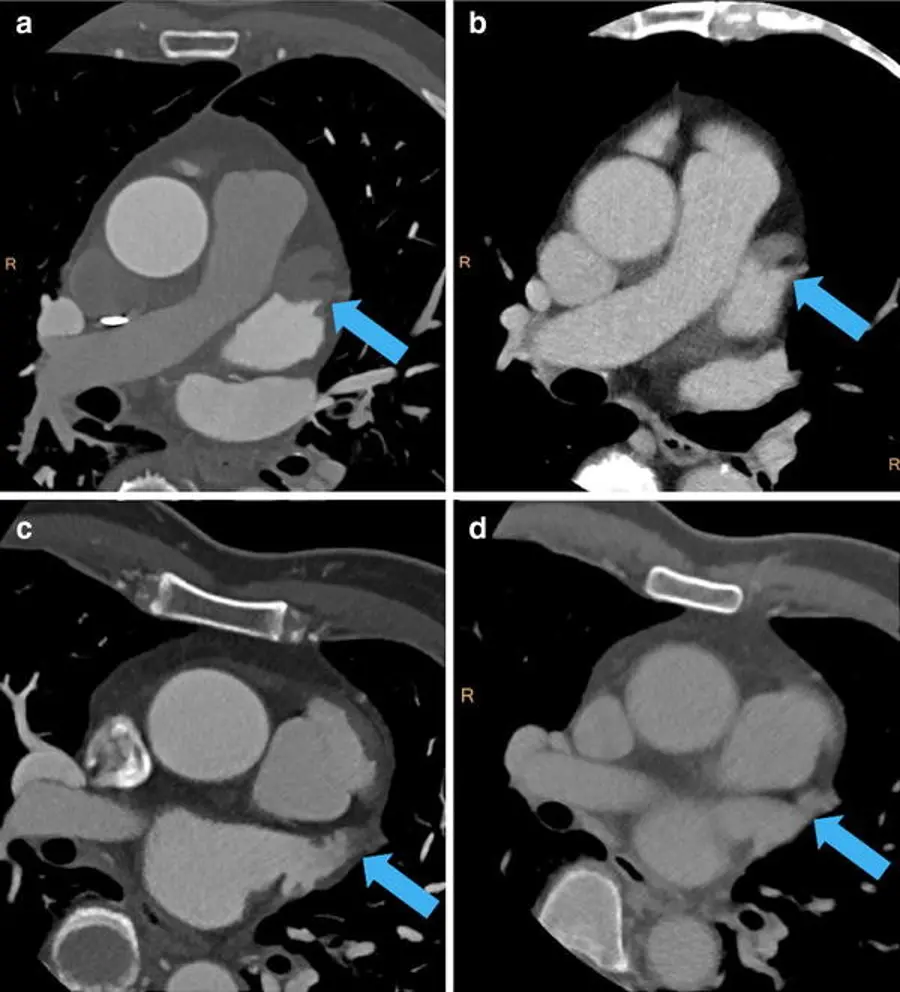

- Evaluate the left atrial appendage

- You want to look to make sure it fills completely with contrast.

- If it doesnât fill completely, it could be suggestive of a thrombus! However, sometimes it wonât fill completely because it takes a while for contrast to fill. In those cases, weâll run a delayed series. This involves scanning the LAA 30 seconds later to see if the contrast doesnât actually fill. If these delayed series are present in our system, youâll see them available in the

Series Listand theyâll be marked Delay.- While we use 30 seconds, other institutions use different times to reassess for delayed contrast filling to r/o thrombus.

- Nice meta-analysis demonstrating the excellent diagnostic accuracy of CT with delayed imaging for detection of LA/LAA thrombus here.

- đ Recall, TEE is considered the gold standard for detect LA/LAA thrombus.

- Arrow highlights LAA thrombus